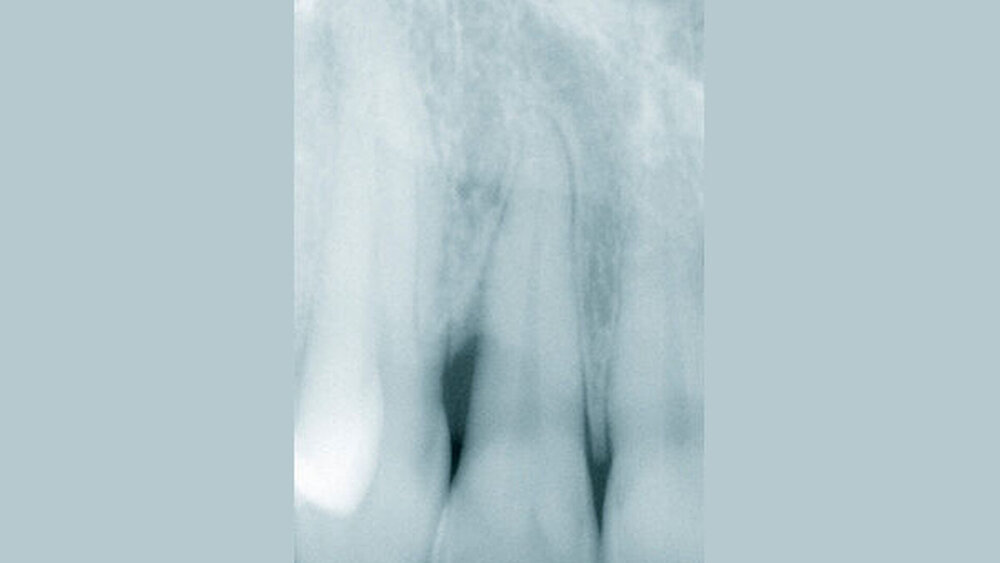

Die Patientin (44 Jahre alt, guter Allgemeinzustand) wies vor Behandlungsbeginn eine befriedigende Mundhygiene mit approximalen Belägen und Sondierungstiefen bis 7 mm auf (Abb. 1).